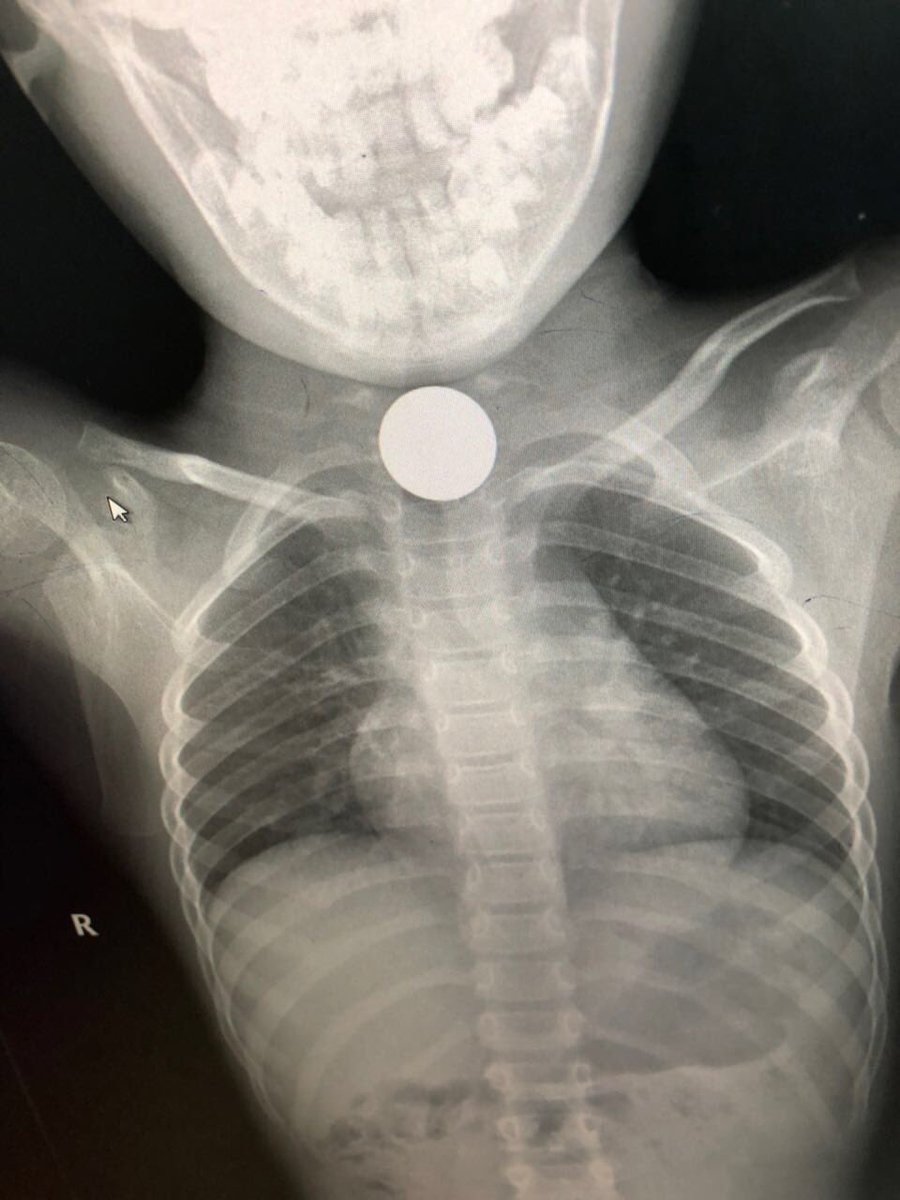

تمكن فريق طبي بمستشفى القريات العام من استخراج جسم معدني من مريء طفلة تبلغ من العمر خمس سنوات، من خلال عملية جراحية دقيقة تكللت بالنجاح بفضل الله.

وقالت صحة القريات، في تغريدة عبر حسابها في “تويتر”، إن الأطباء قرروا إجراء العملية للطفلة بعد أن أظهرت صور الأشعة التي أجريت لها وجود جسم معدني غريب في الجزء الأعلى من المريء.

وأضافت صحة القريات: “إن العملية الجراحية تمت بنجاح، وإن الطفلة الآن بحالة جيدة”.